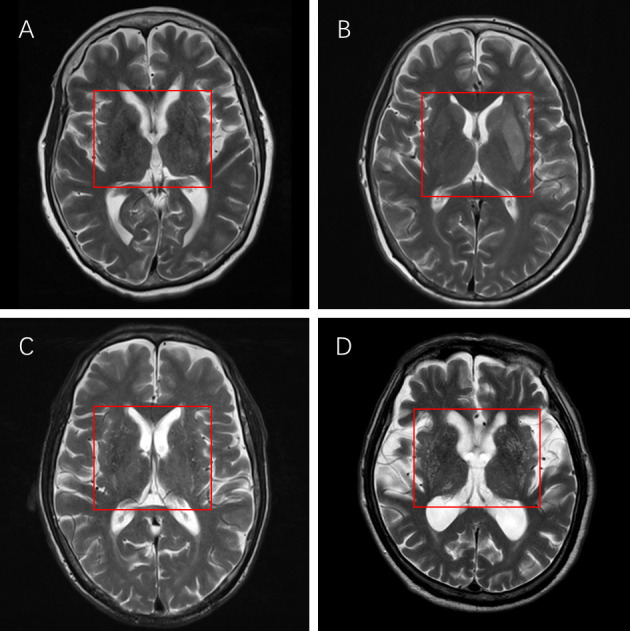

Method: A matched case-control study was conducted in Xiamen, China. A total of 184 IS patients (cancer vs control=1:1) were recruited. The severity of BG-EPVS was graded using high-resolution MRI. Patients' gender, age, clinical risk factors, other imaging changes and laboratory findings information at admission were collected. Logistic regression models were constructed and subgroup analysis by cancer treatment.

Abstract Image